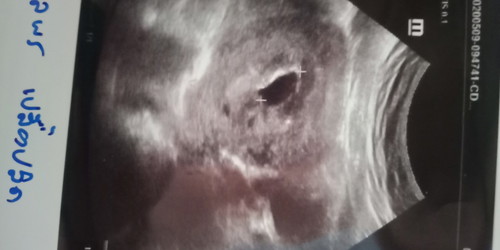

ใครดูออกบ้างคะ

มันมีเลือดออกไปซาวมาเปยแบบนี้ หมอนัดอีกที่งันที่19เดือนนี้ึคะ

อันนี้น่าจะเป็นถุงตั้งครรภ์ค่ะ ยังไม่เจอน้อง